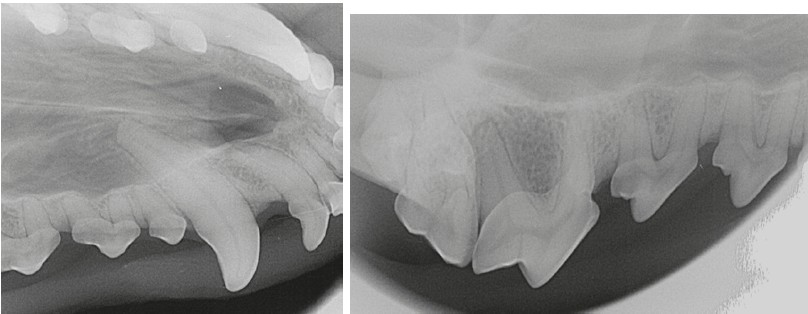

Fig. 5. Intraoral radiograph for stage 1 dental calculus

Source: VTC "Dentalvet".

Fig. 6. Dental calculus: a — stage 1 (409 tooth) and stage 3 (404 tooth); б — stage 2 (409–405 teeth); в and г — intraoral radiograph for stage 2 dental calculus.